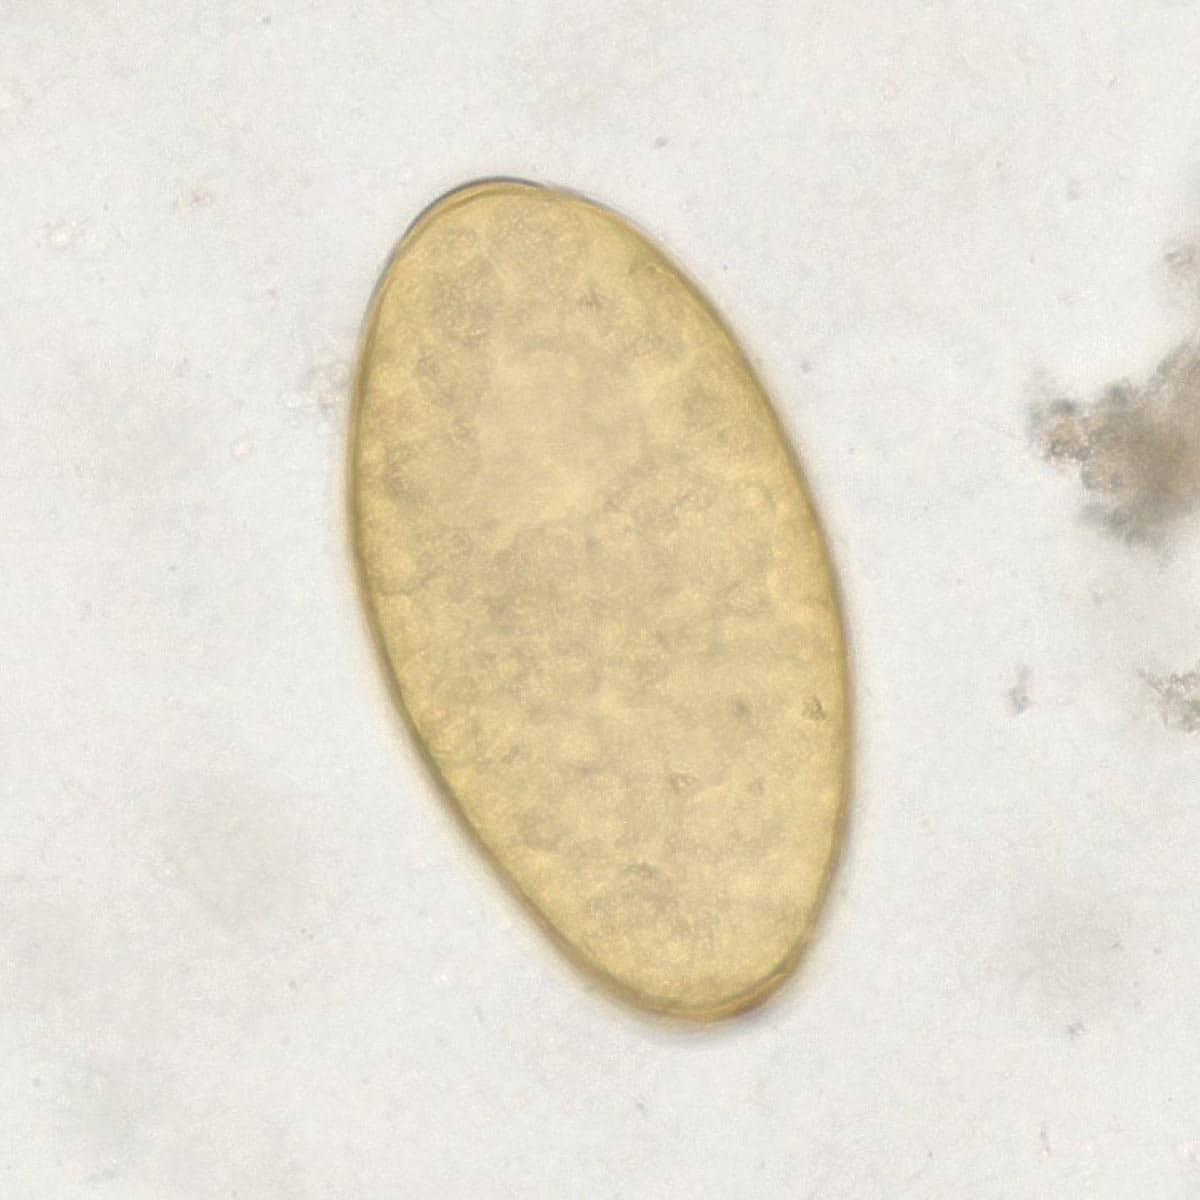

Automatic detection over 30 species

Built on worldwide parasite-positive specimens, ParaScout AI identifies a vast number of parasite species, including those that are clinically rare or challenging to find.